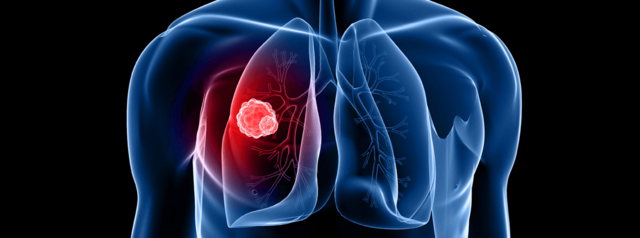

El cáncer de pulmón es el crecimiento de células desordenadas que se forman en los tejidos del pulmón, generalmente en aquellas que recubren los conductos del aire. Así lo explica el doctor Andrés Franco, cirujano de tórax de la Clínica del Occidente, quien además cuenta que este cáncer es una de las principales causas de muerte tanto en hombres como en mujeres.

“El cáncer de pulmón se caracteriza por ser una enfermedad silenciosa en sus inicios. Cuando aparecen síntomas como tos permanente ocasionalmente con sangre, dolor en el pecho o en la espalda, ronquera y pérdida de peso sin explicación, significa que el cáncer ya está avanzado”, explica el doctor Franco.

El especialista también comenta que cuando aparecen estos síntomas se deben realizar exámenes como la radiografía de tórax, donde eventualmente se pueden observar masas pulmonares que posteriormente van a estudio y demuestran si hay cáncer.